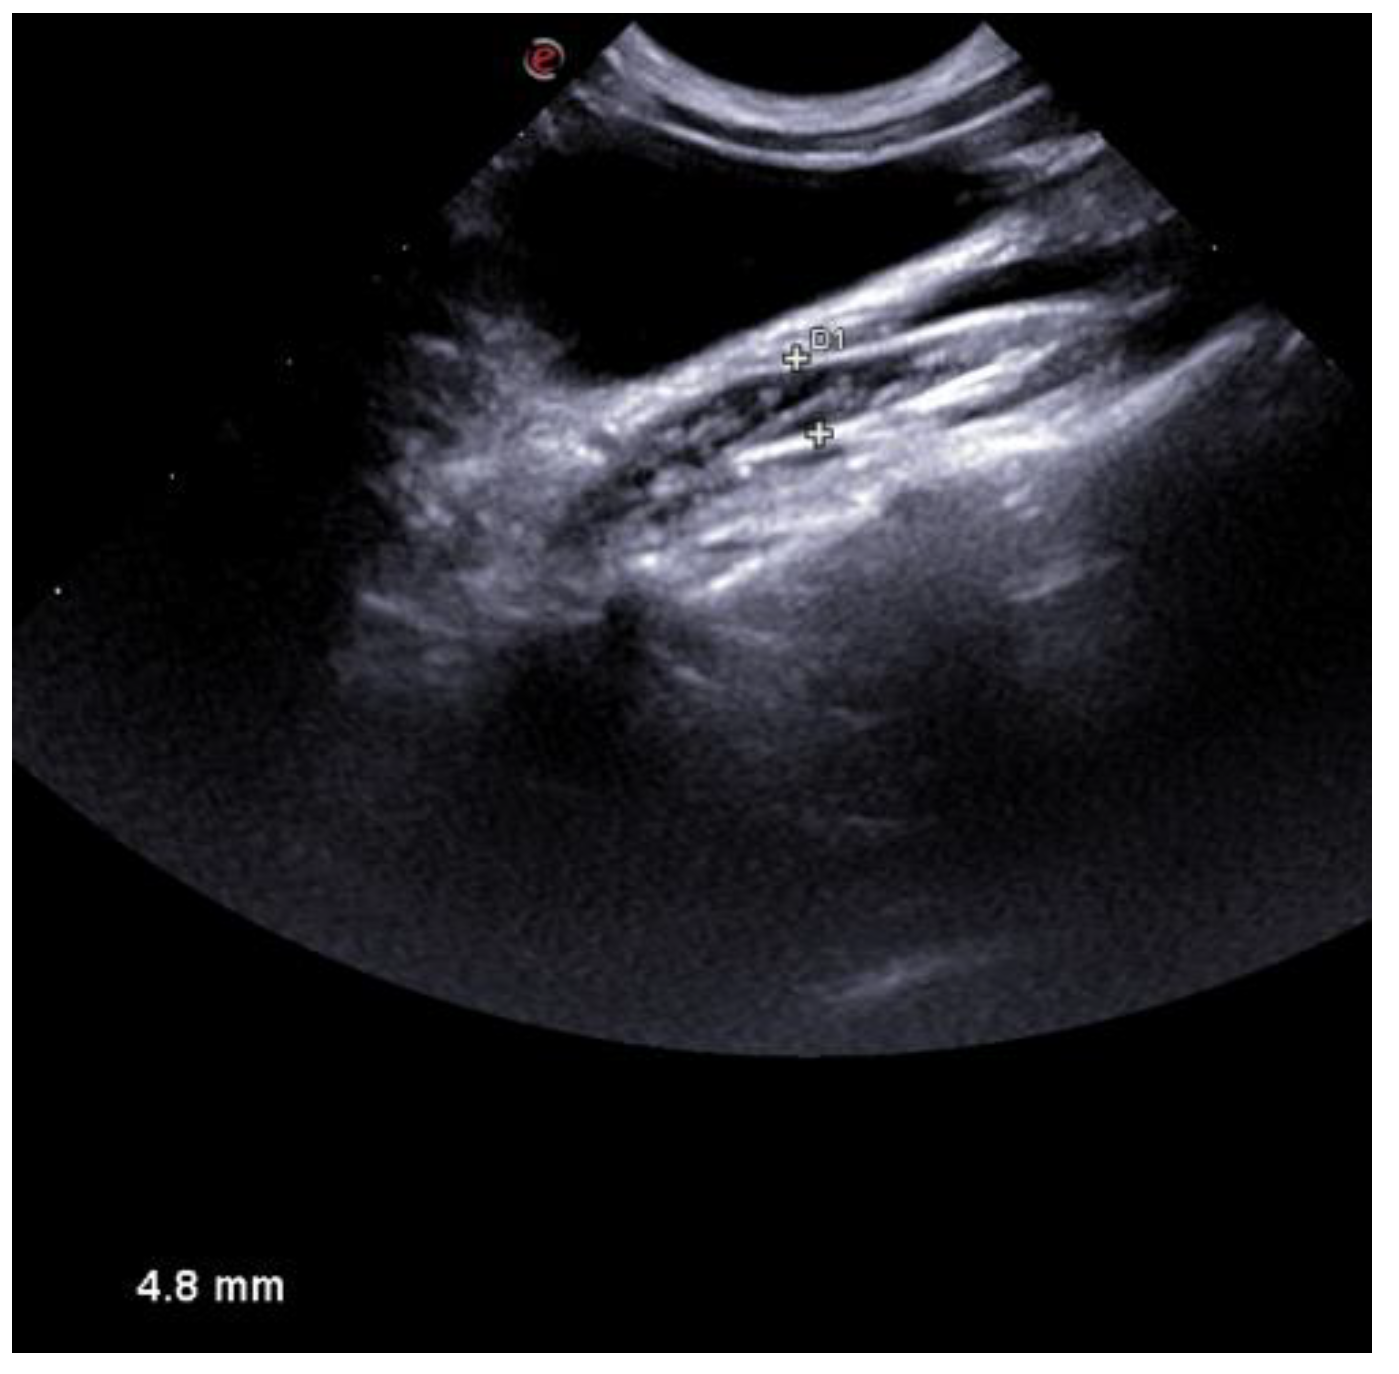

2. History and Clinical Findings

3. Treatment and Follow up